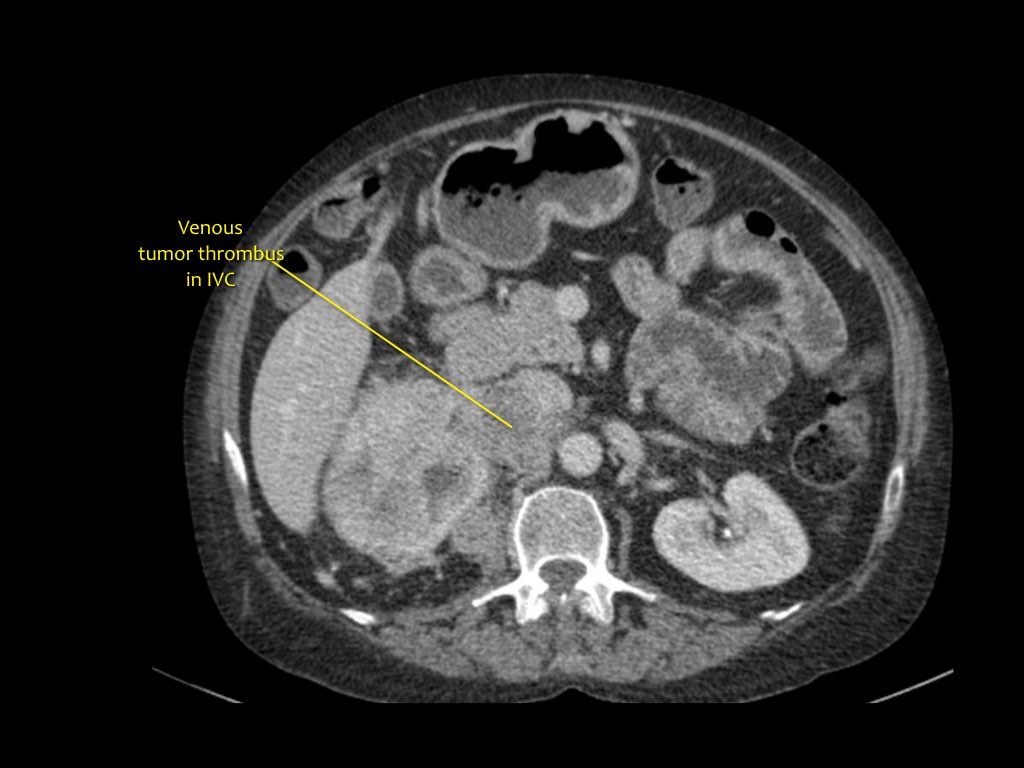

Phân giai đoạn RCC

RCC có thể xâm lấn mỡ quanh thận vượt qua cân thận và có thể lan vào tĩnh mạch thận, tĩnh mạch chủ dưới (IVC) hoặc tuyến thượng thận cùng bên.

Đối với phẫu thuật viên, điều quan trọng là cần biết có huyết khối u trong IVC hay không và liệu huyết khối có lan vào lồng ngực trên cơ hoành hay không (cần có phẫu thuật viên lồng ngực trong ca mổ).

Khoảng 25% bệnh nhân đã có di căn tại thời điểm chẩn đoán.